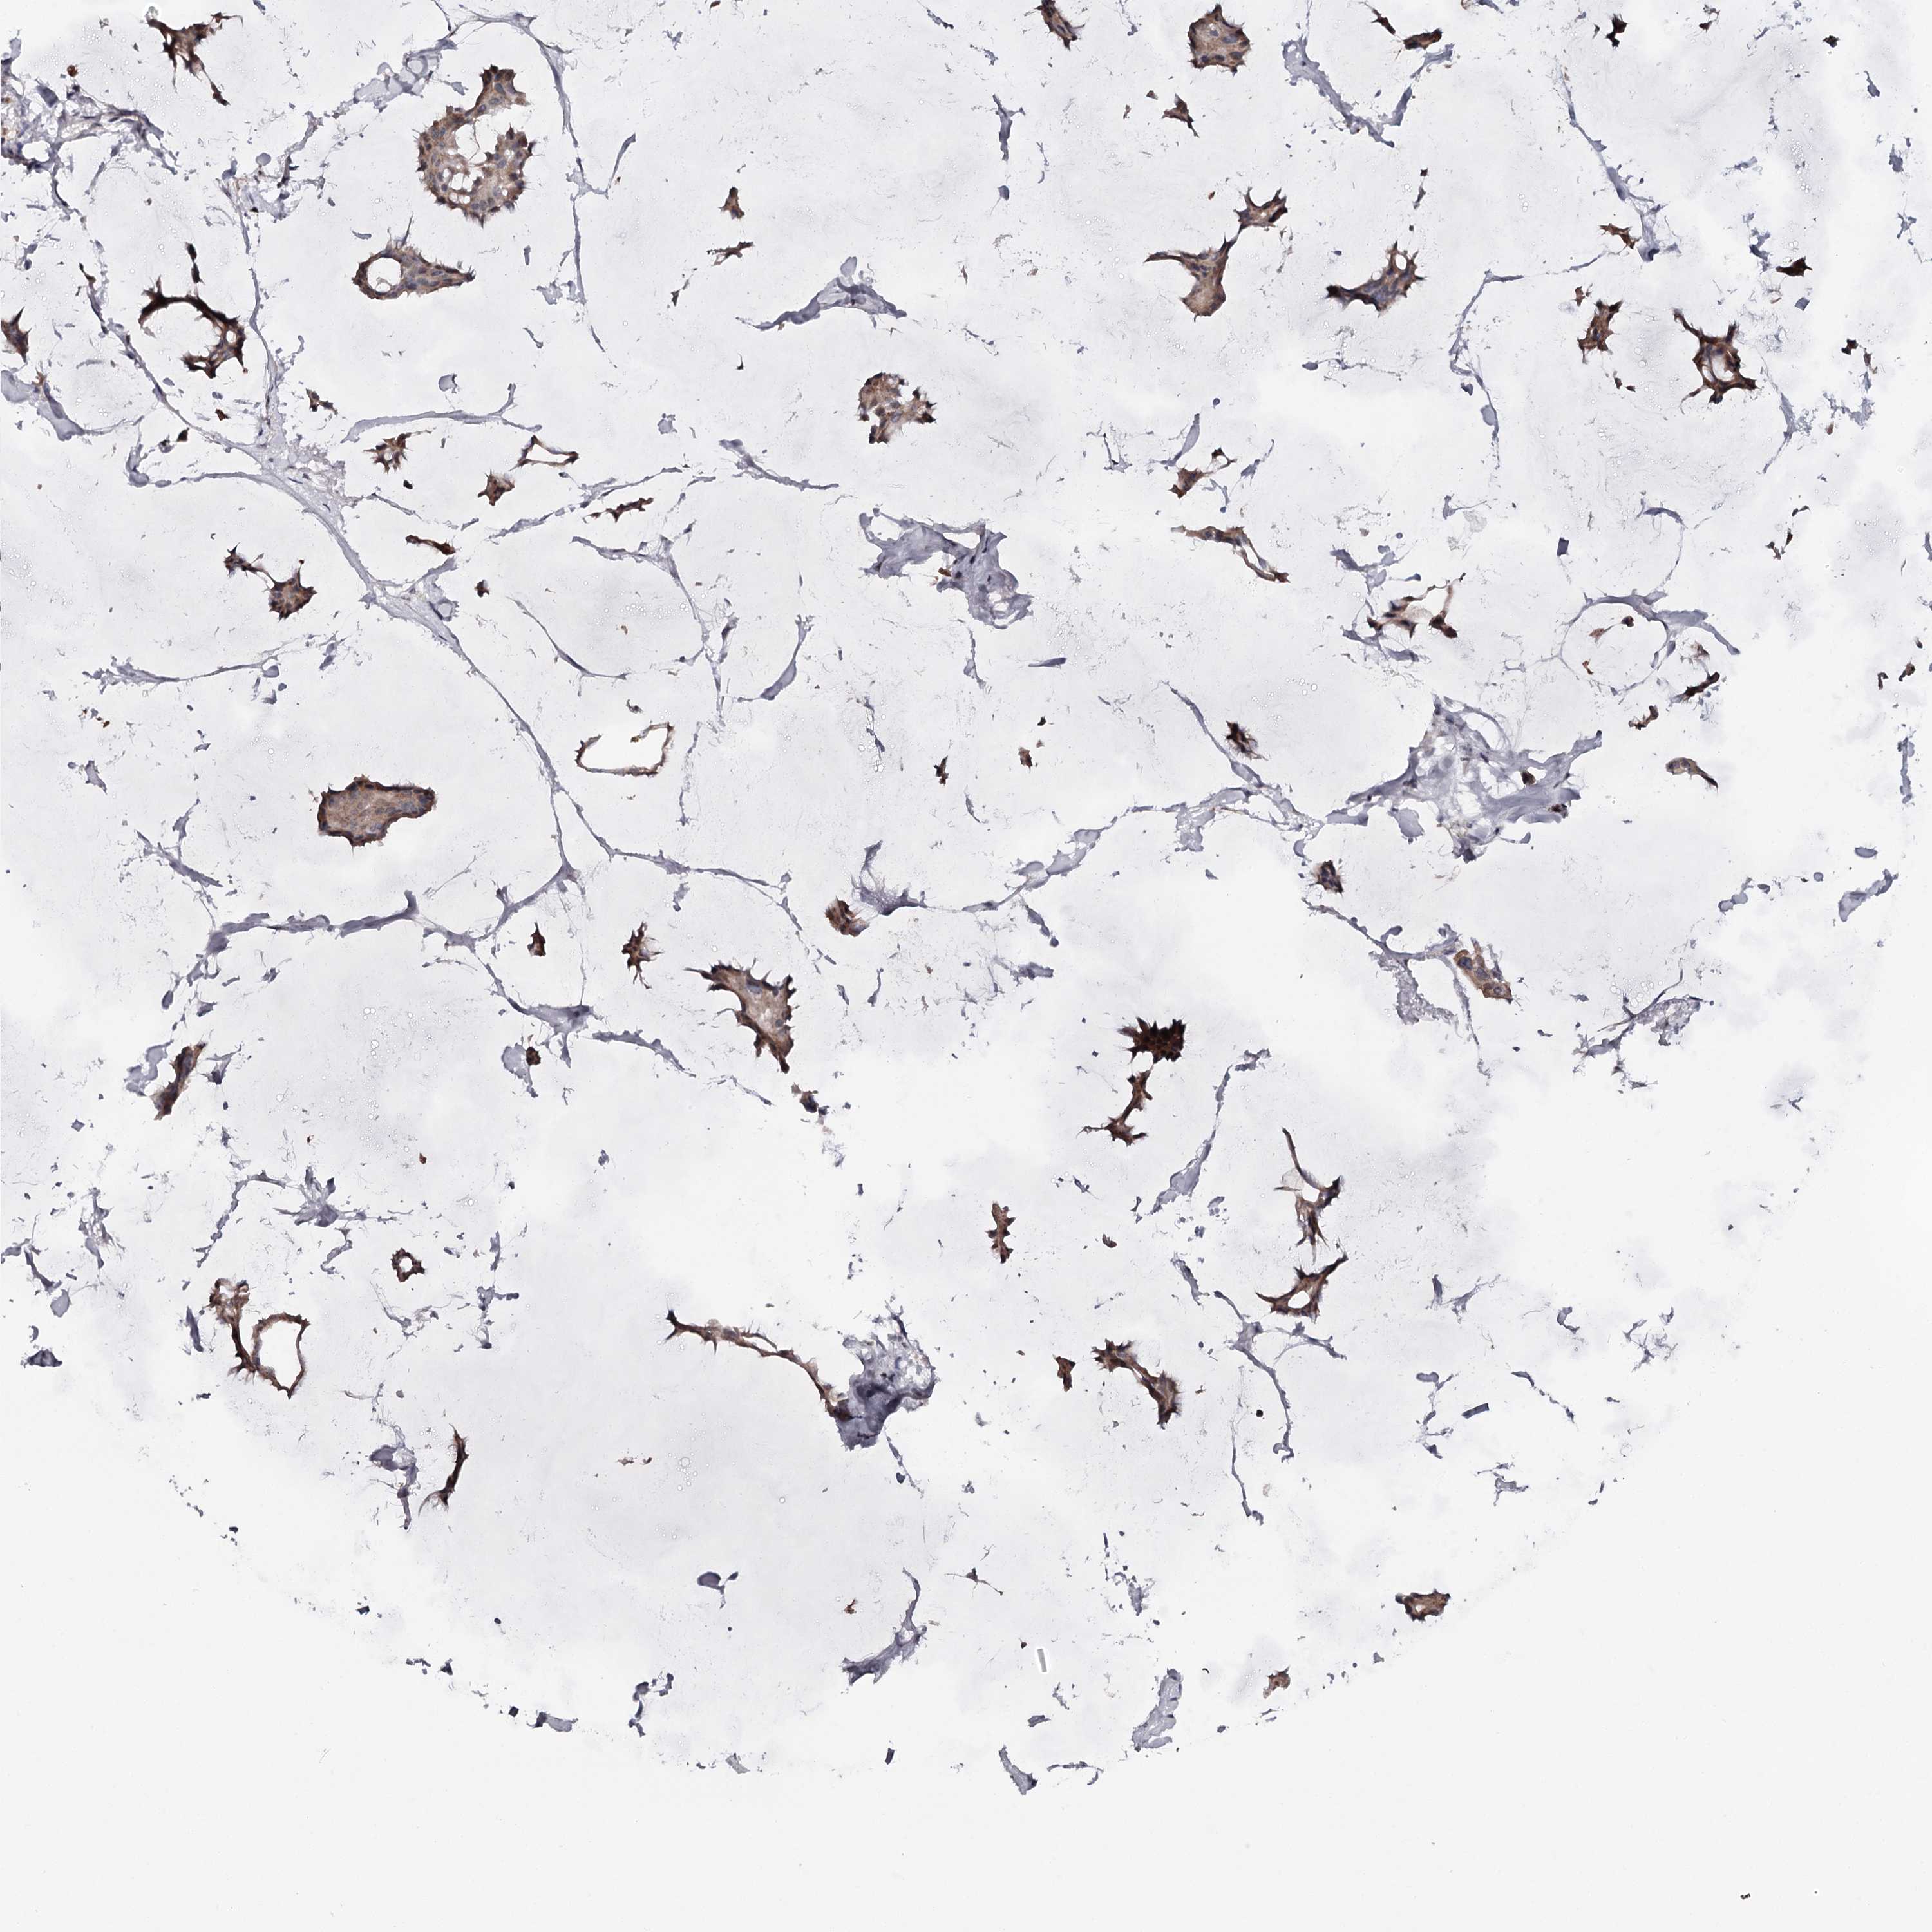

BRCA TCGA BRCA VALIDATION PROTEIN EXPRESSION

ANTIBODIES

AND

VALIDATION